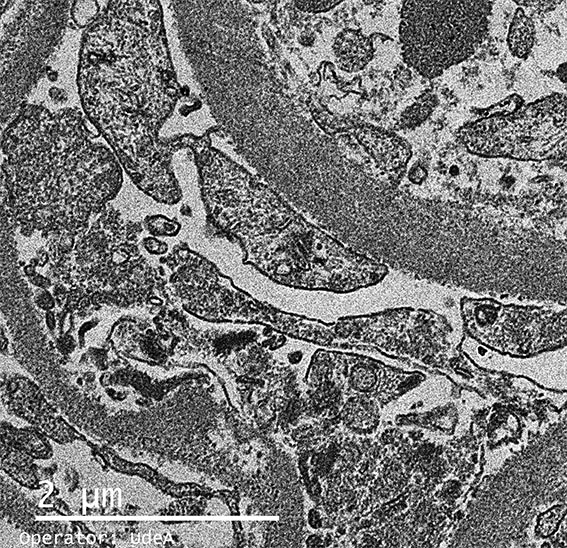

The patient is a 4-year-old girl who presented nephrotic syndrome in the first year of life, with biopsy in which focal segmental glomerulosclerosis was diagnosed. There was no response to multiple treatments. Molecular studies were unable to detect a specific genetic alteration. He developed ESRD at 3 years of age. She was in hemodialysis few months and was transplanted from a dead donor. Nephrectomy of a native kidney was done. Before the transplant, on dialysis, she had low urine output and non-nephrotic proteinuria without hypoalbuminemia or dyslipidemia. After transplantation presented progressive increase in proteinuria. Four post-transplant weeks there was complete nephrotic syndrome with proteinuria >100 mg/m2/h, dyslipidemia and hypoalbuminemia. Serum creatinine 0.5 mg/dL.

A renal biopsy was done, see the images.

Figure 8. Electron microscopy, X4,000.